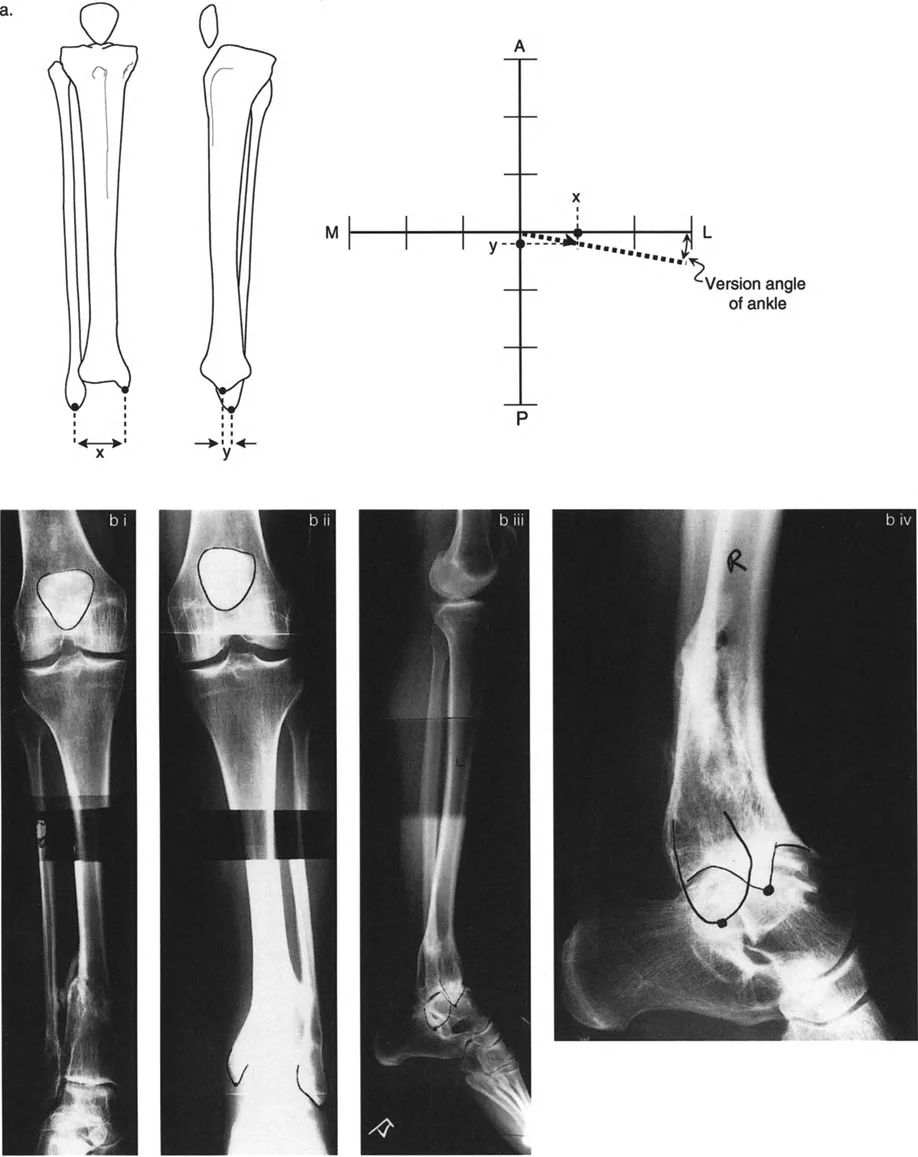

تحليل دوران قصبة الساق (Tibial Torsion Analysis)

يتبع تحليل دوران قصبة الساق (Tibial Torsion) منطقاً مشابهاً ولكنه يعتمد على معالم تشريحية مختلفة (الكاحلين). يحدد هذا التحليل مدى التواء عظم قصبة الساق.

1. بروتوكول التصوير: يتم الحصول على صورتين بالأشعة السينية (AP و Lateral) للكاحل مع توجيه صابونة الركبة للأمام.

2. القياس: يتم قياس المسافة العرضية بين الكاحل الإنسي والوحشي على كلتا الصورتين.

3. الرسم البياني: يتم رسم هذه القيم على رسم بياني للمستوى المائل لتحديد اتجاه مستوى الكاحلين.

4. المقارنة: تُقارن زاوية الدوران المحسوبة بالجانب الآخر السليم أو بالنطاق الفسيولوجي الطبيعي (عادة 15° ± 5° من الدوران الخارجي).

بالإضافة إلى الأشعة السينية المتخصصة، قد يطلب الأستاذ الدكتور محمد هطيف صوراً مقطعية (CT Scans) أو رنيناً مغناطيسياً (MRI) للحصول على رؤية ثلاثية الأبعاد أكثر تفصيلاً للعظام والأنسجة الرخوة والأعصاب، خاصة في الحالات المعقدة أو عند التخطيط الجراحي الدقيق.

تحديد مستوى التشوه بدقة

إن تحديد المستوى الدقيق للتشوه الدوراني هو أحد أهم الخطوات في التخطيط الجراحي. على الرغم من أن الدوران هو تشوه زاوي في المستوى المستعرض، إلا أن موقعه على طول العظم (قريب من المفصل أو بعيد عنه) يؤثر بشكل كبير على كيفية تصحيحه وتأثيره على الأنسجة المحيطة.